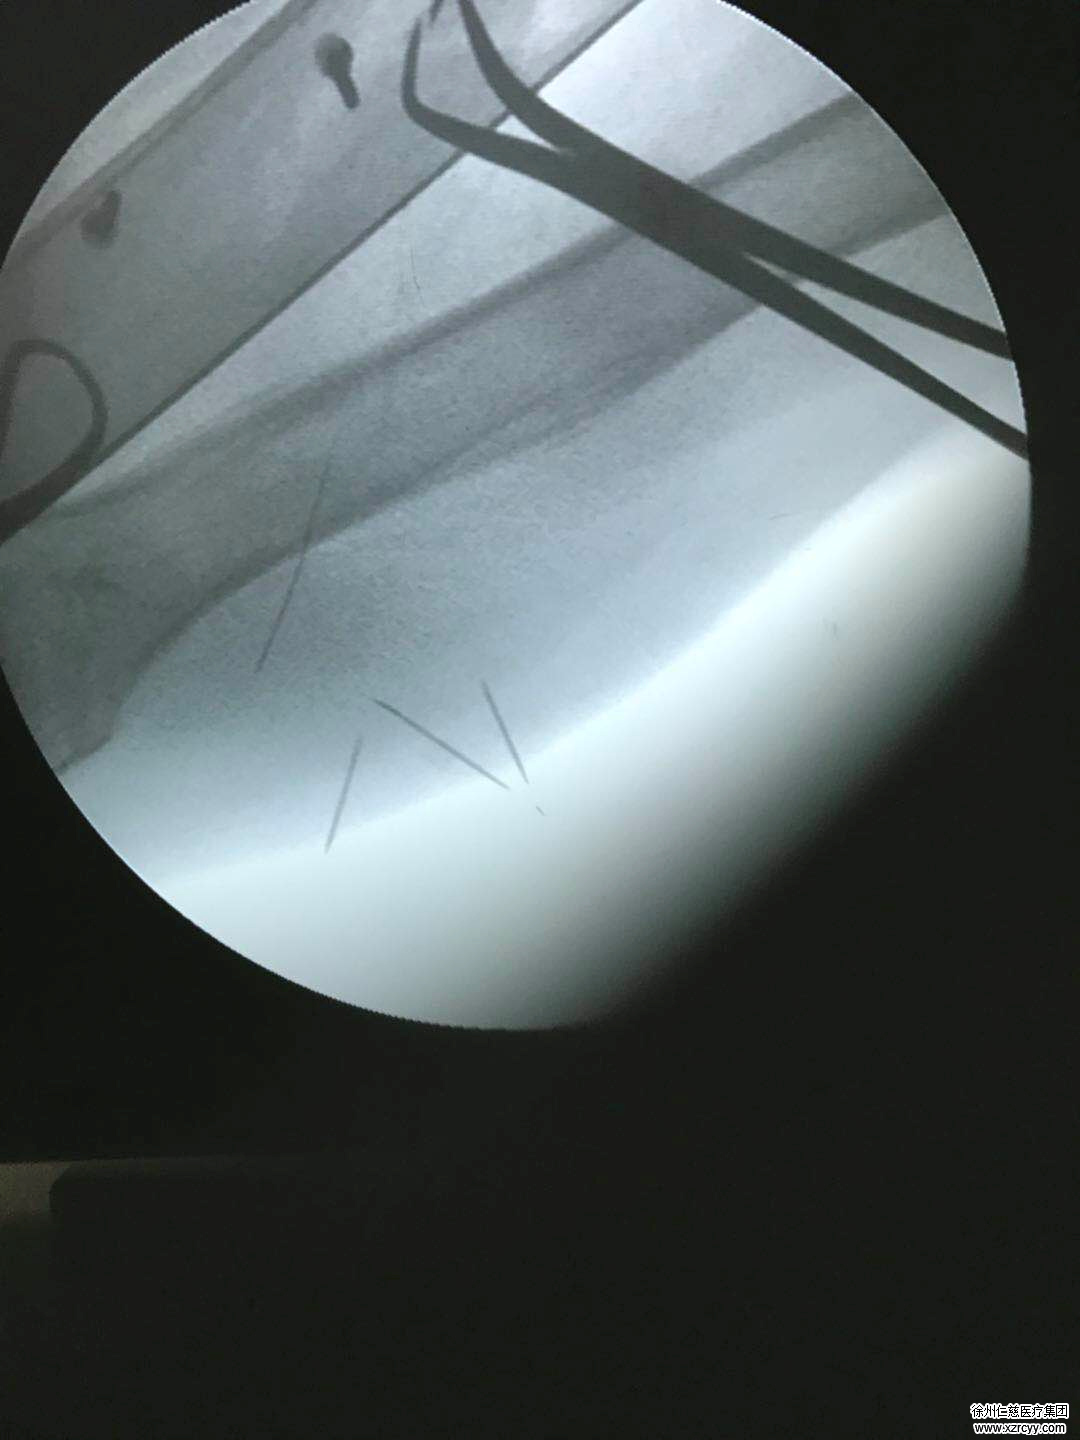

在betway在线登陆,手外科一病区主任李甲安排郑老太接受X线检查,结果发现,郑老太的左臂下侧针眼处已经形成血肿,而CR片子正中赫然显示郑老太的左臂下侧中有一根长约5厘米,跟注射器上的针头一样长的针灸断针!事不宜迟,李甲医生考虑到郑老太的年龄,且针灸用针又细又软,随着肌肉运动收缩,可能四处“游离”,犹如一颗小石子掉进沙堆,要准确“定位”断针位置很困难,因为郑老太刚做完检查与进手术室这个期间,断针都可能“移位”!

术中,李医生进行再次定位,因为针灸断针随着肌肉运动收缩,可能四处“游离”,只能按照解剖层次一点一点往下走,根据C型臂的定位,终于在距离定位点3cm的肌肉层内找到了这根惹事的断针!大家松了一口气,李甲主任随即迅速的拔出了这根惹事的断针。